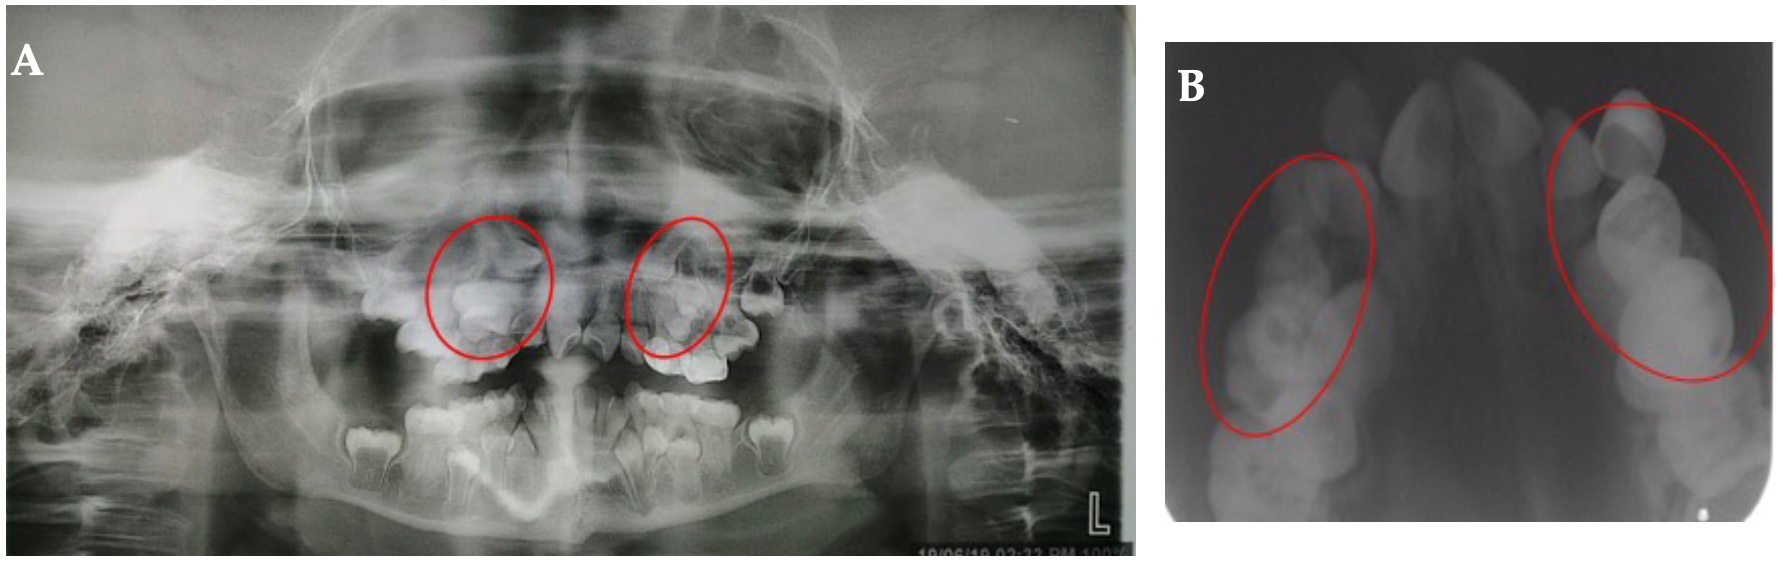

Radiográficamente, vía de erupción anómala de caninos y primeros premolares superiores, así como persistencia de caninos y molares primarios superiores, trazo sugerente de fractura antigua en región parasinfisiaria izquierda. (Figura 2:A, B) El departamento de Estomatología del Instituto Nacional de Pediatría de acuerdo a un análisis clínico y radiográfico, diagnosticó edad dental de 8,3 de acuerdo al método de Demirjian, falta de espacio para erupción de la dentición permanente, vía de erupción anómala de caninos y primeros premolares, riesgo de resorción externa por presión a los órganos dentarios erupcionados; presencia de diversas persistencias dentales superiores, se decidió tratamiento con extracciones de dichos órganos dentarios. En la arcada inferior no fue llevado a cabo ningún tratamiento, debido a no presentar vía de erupción anómala. Se pautó plan de tratamiento con Cirugía Maxilofacial, se interconsultó al servicio de Endocrinología, quienes indicaron pausa en el tratamiento (drug holiday) de 3 meses. Previa firma de consentimiento informado por parte de sus padres, se administró amoxicilina 50 mg/kg 1 hora antes, bajo anestesia general, con intubación naso traqueal, se realizó doble colgajo semi Newman para osteotomía, extracción de los caninos y molares primarios superiores y enucleación de los caninos y primeros premolares superiores. Previo a la cirugía, se le indicó a la paciente realizar enjuagues con gluconato de clorhexidina al 0,12% 2 veces al día durante 5 días y de igual manera postoperatoriamente. (Figura 3:A)

Figura 2: Radiografías: A. Panorámica. B. Oclusal